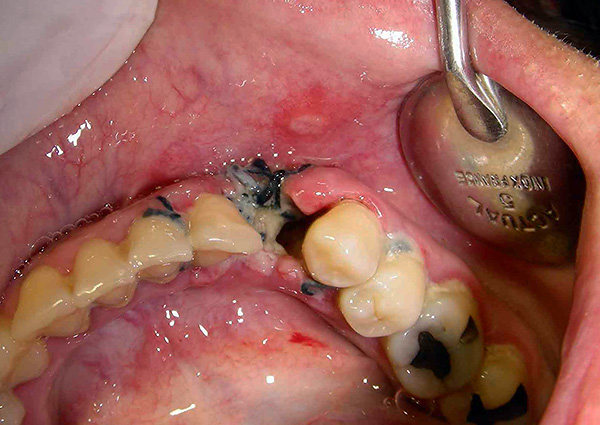

L'immagine sotto mostra un dente del giudizio semi-rinforzato:

Non farti prendere dal panico subito. Di solito, l'edema raggiunge il massimo entro 2-3 giorni dopo la rimozione del dente del giudizio, e qui è importante controllare la condizione nel suo insieme e non solo un sintomo. Se c'è un grave deterioramento della salute (febbre a valori elevati, dolore insopportabile che non può essere fermato nemmeno dagli analgesici, suppurazione o sanguinamento dal buco), è necessario consultare immediatamente un medico.